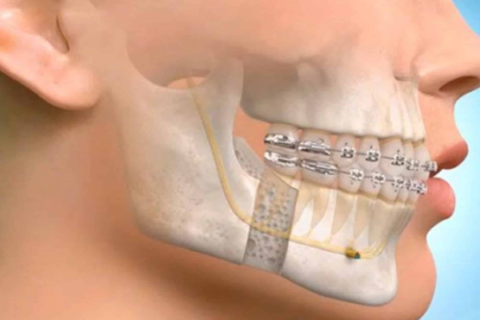

Corrective/Esthetic Jaw Surgery

Improving bite, symmetry, and facial appearance through surgery.